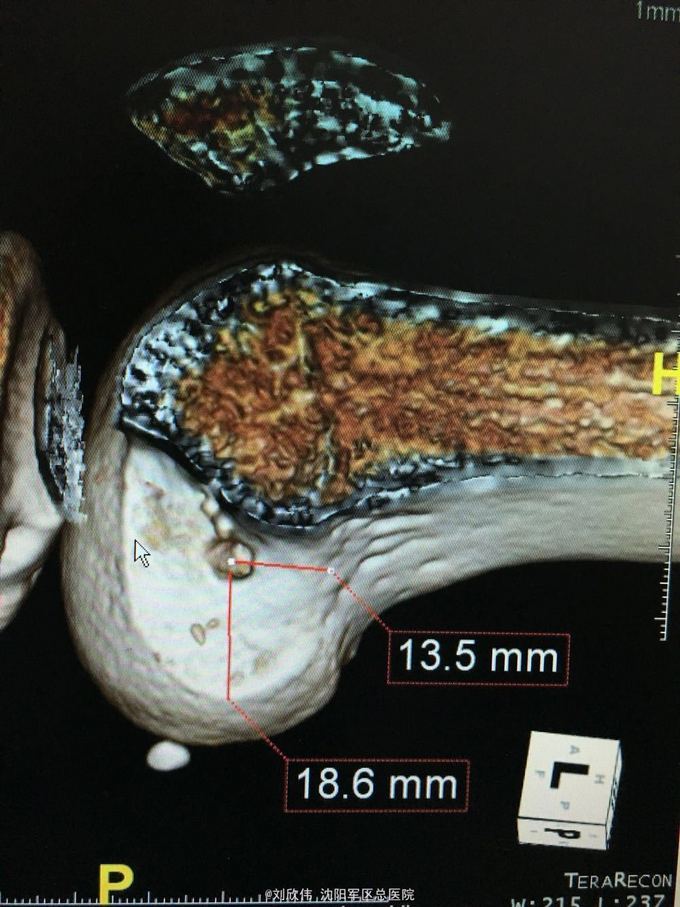

右膝前交叉韧带断裂 右膝半月板损伤 手术方法如题,直接上图

这个病例术后汇付的非常快 值得讨论的是acl重建时,股骨隧道内口的选择还是很有讲究的,目前从AM入路建立隧道点很热,但是,说是解剖重建,术中确实很多人选的点确是等长点,由于我们LARS韧带也做,所以这点体会有味深刻 解剖点的位置相比等长点,是比较偏下的(屈膝90°,关节镜操作时的角度而言),偏向平台关节面,这样虽然解剖,但会导致股骨隧道长度过短。需要注意